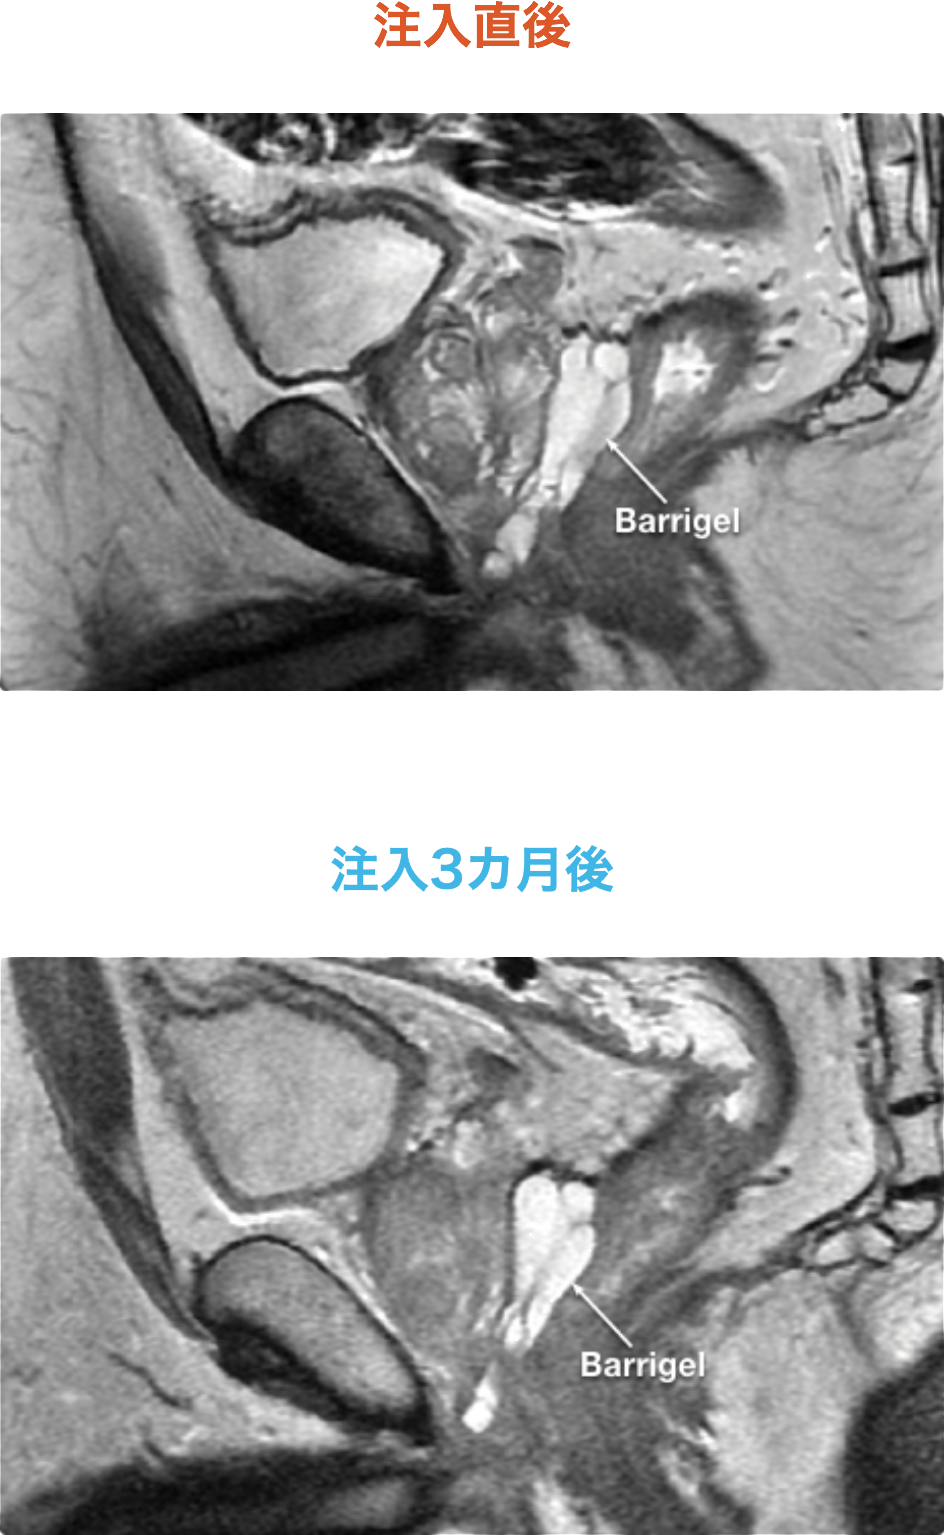

吸収時にも安定したスペースが認められた

患者の例